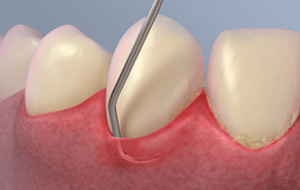

Scaling and Root Planing

Scaling and root planing is a careful cleaning of the root surfaces to remove plaque and calculus [tartar] from deep periodontal pockets and to smooth the tooth root to remove bacterial toxins.